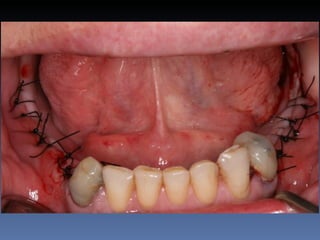

Plano de tratamento: Exodontia 3.1 , seguida de

instalação de implante com função imediata e

reabilitação provisória fixa.

Isolamento da área cirúrgica com luva estéril.